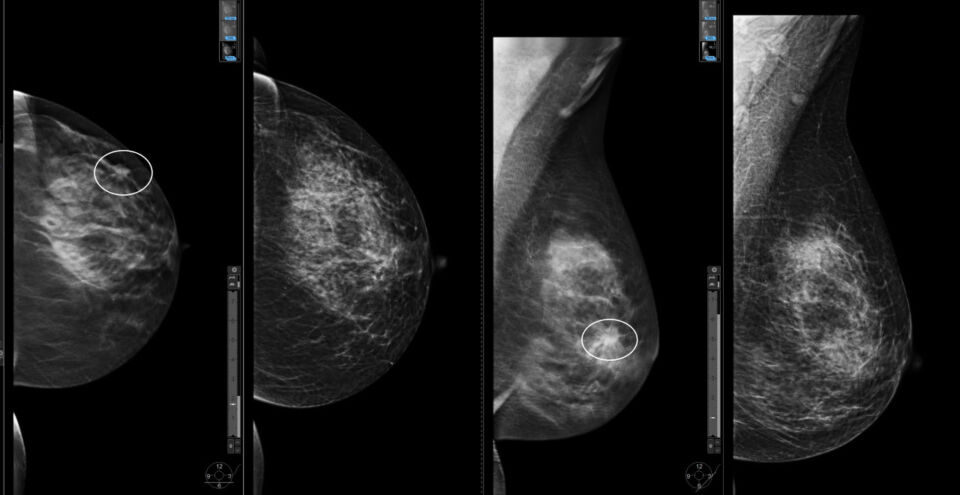

Новое исследование шведских ученых, опубликованное в British Medical Journal (BMJ), показало, что у женщин, пропускающих первую маммографию, риск смерти от рака молочных желез в течение последующих 25 лет повышается на 40%.

Во время проведения исследования эксперты из Каролинского института изучили судьбы около полумиллиона женщин, приглашенных на маммографию в период с 1991 по 2020 годы. Все участницы находились под наблюдением в течение 25 лет.

При этом около трети из них (32%) проигнорировали первый скрининг. Женщины из этой группы также впоследствии проходили обследования нерегулярно, из-за чего у них чаще диагностировали рак груди на поздних стадиях.

Уровень заболеваемости в обоих группах женщин (тех, что посетили первый скрининг и тех, которые пропускали обследования) был одинаковым, разница заключалась лишь во времени диагностики: женщины, проигнорировавшие первое приглашение, чаще узнавали о болезни на поздних стадиях.

За 25 лет наблюдения уровень смертности от рака молочной железы среди тех, кто не прошел первое обследование, составил 9,9 случая на тысячу женщин. У тех, кто обследовался вовремя, этот показатель был ниже — семь летальных исходов на тысячу.